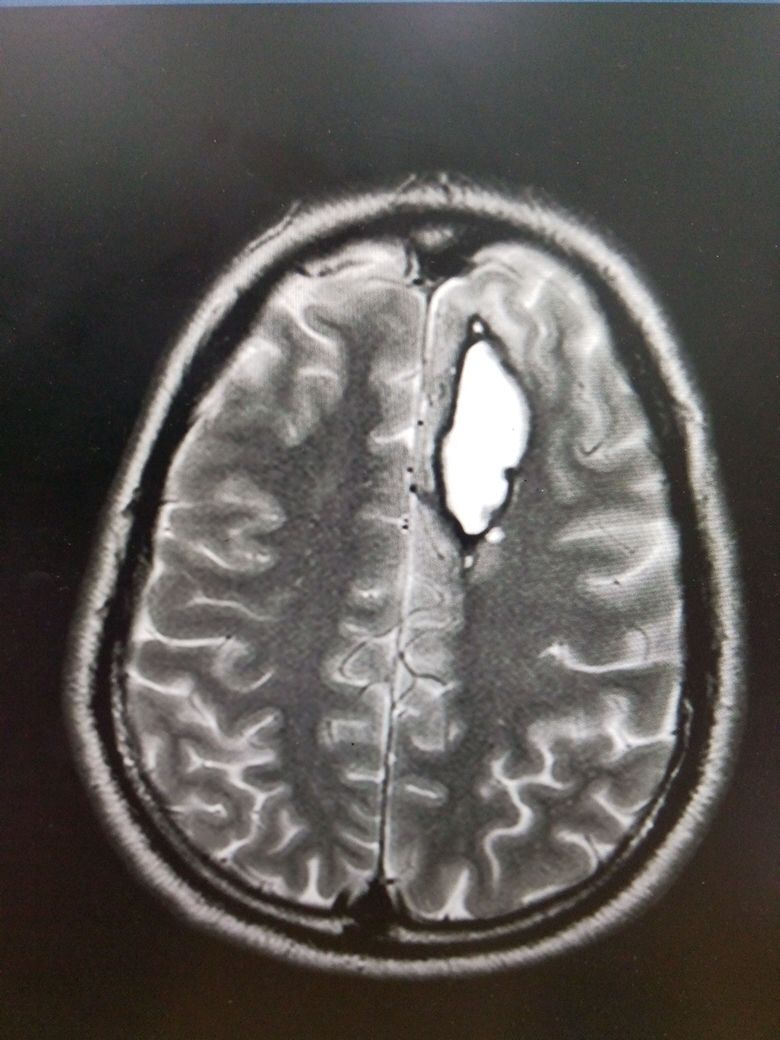

ሴሬብራል አኑኢሪዝም   Cerebral Aneurysm

ሴሬብራል አኑኢሪዝም በአንጎል ውስጥ ባለው የደም ቧንቧ ዝውውር ላይ በደካማ ቦታዎች ላይ የሚከሰቱ መዘዞች በመባል ይገለጻሉ። አብዛኛዎቹ ሴሬብራል አኑኢሪዜም ጸጥ ያሉ ናቸው እና በአጋጣሚ በኒውሮኢሜጂንግ ወይም በሬሳ ምርመራ ላይ ሊገኙ ይችላሉ። በግምት 85% የሚሆኑት አኑኢሪዜም በቀድሞው የደም ዝውውር ውስጥ ይገኛሉ ፣ በተለይም በዊሊስ ክበብ ውስጥ ባሉ መጋጠሚያዎች ወይም መጋጠሚያዎች ላይ። Subarachnoid የደም መፍሰስ (SAH) ብዙውን ጊዜ የሚከሰተው ከመጥፋት ጋር ሲሆን ከከፍተኛ የበሽታ እና የሞት መጠን ጋር የተያያዘ ነው. ይህ እንቅስቃሴ ሴሬብራል አኑኢሪዜም ያለባቸውን ታካሚዎችን በመንከባከብ የተውጣጡ ባለሙያዎች ቡድን ሚናውን ጎላ አድርጎ ያሳያል።

Cerebral aneurysms are defined as dilations that occur at weak points along the arterial circulation within the brain. The majority of cerebral aneurysms are silent and may be found incidentally on neuroimaging or upon autopsy. Approximately 85% of aneurysms are located in the anterior circulation, predominately at junctions or bifurcations along the circle of Willis. Subarachnoid hemorrhage (SAH) usually occurs with rupture and is associated with a high rate of morbidity and mortality. This activity highlights the role of the interprofessional team in caring for patients with a cerebral aneurysm.

ለምንጩ እና ለበለጠ መረጃ እዚህ ወይም ፎቶወቹን ይጫኑ Click here or on the images for source and to read more